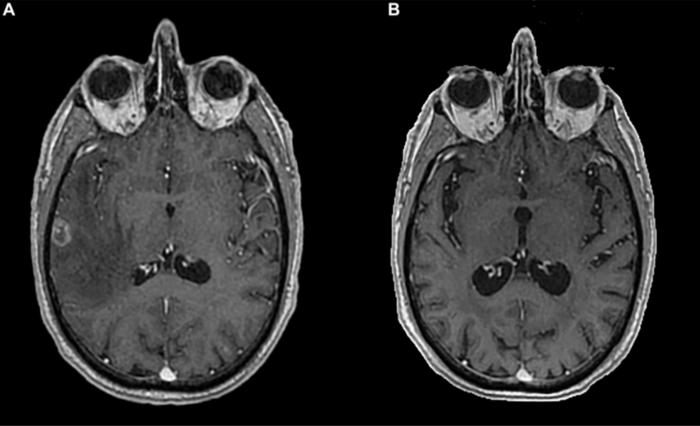

Researchers Mafalda Costa and Helena Magalhães from the Department of Medical Oncology, Hospital Pedro Hispano in Matosinhos, Portugal present the case of a 51-year-old man diagnosed with stage IV non-small cell lung cancer (NSCLC) and brain metastasis. After undergoing whole brain radiotherapy (WBRT), the patient achieved both intracranial and extracranial complete response following second-line treatment with an immune checkpoint inhibitor. Currently, he has an overall survival of 87 months and a progression-free survival of 73 months, maintaining an optimal quality of life.